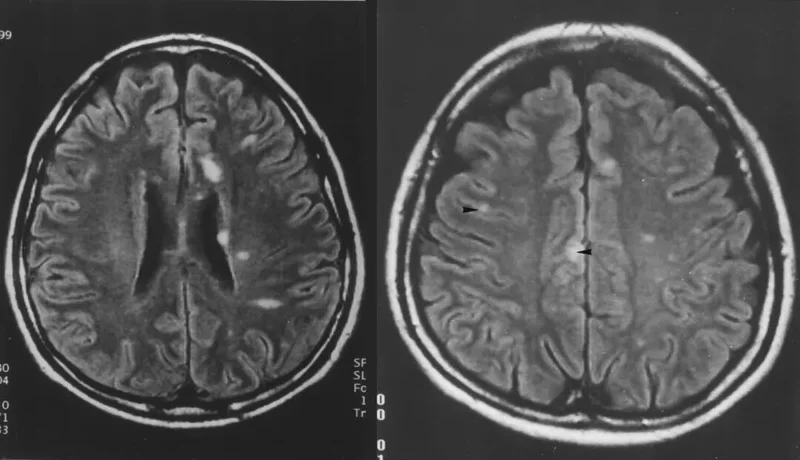

尼帕脑炎患者的脑部病灶(白色部分)

(图:ajronline.org)▼